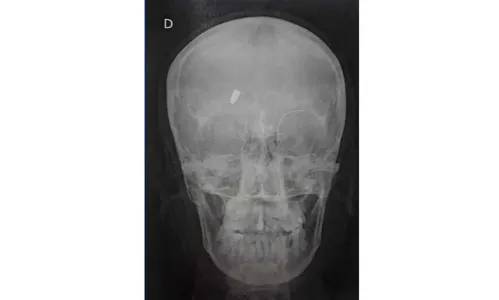

No local, uma profissional de saúde informou à mulher que ela havia levado um tiro e que a munição estava alojada. A princípio, a munição seria de calibre 22.

Às 20h30, a Polícia Militar (PM) foi acionada para comparecer na unidade hospitalar. Aos agentes, a paciente disse que não sabia de onde veio o tiro.